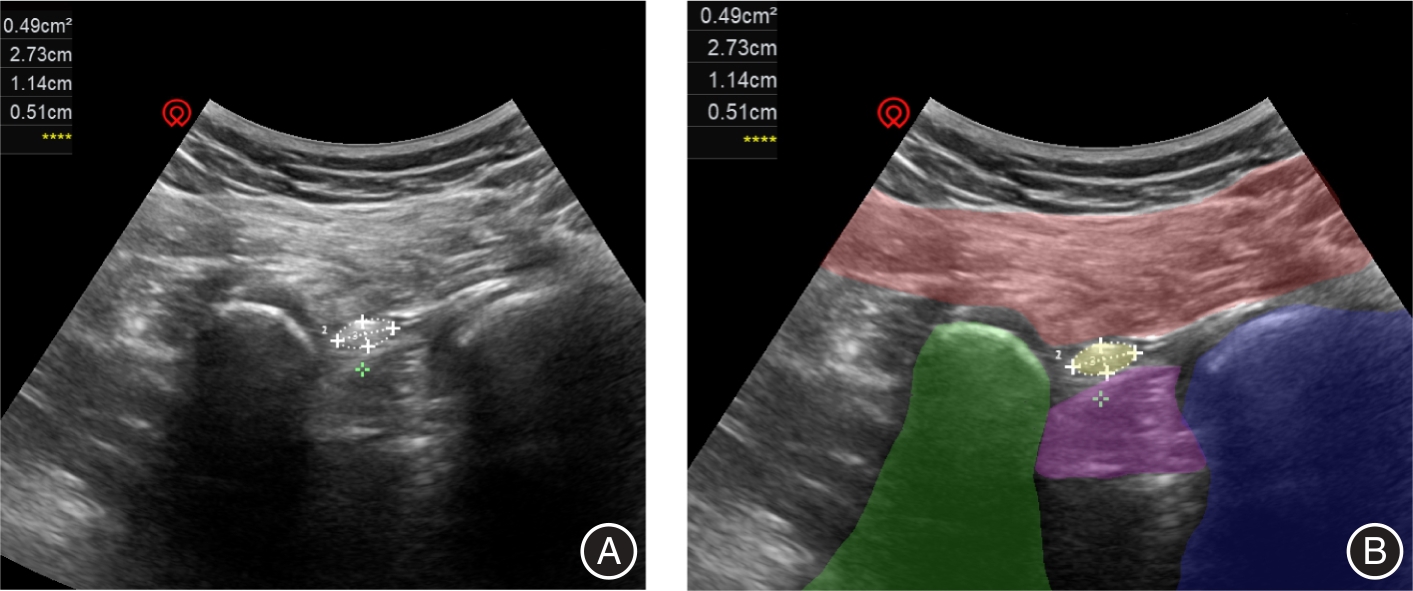

目的 观察内镜手术治疗单侧腰椎间盘突出症的早期临床疗效与坐骨神经横截面积变化之间的关系。 方法 招募2023年6月至2024年6月南昌大学第一附属医院疼痛科52例(n = 52)单侧腰椎间盘突出症患者为研究对象,在手术前以及手术后第4天使用超声测量双侧臀部坐骨结节-股骨大转子水平坐骨神经横截面积值(cross sectional area,CSA),计算坐骨神经横截面积变化△CSA、坐骨神经肿胀率(sciatic nerve swelling rate,SR-SN)。收集患者BMI值(body mass index)、术前、术后第4天视觉模拟量表(Visual Analogue Scale,VAS)、日本骨科协会评分(Japanese Orthopaedic Association Score,JOA)、Oswestry残疾指数(oswestry disability index,ODI)和治疗改善率(treatment improvement rate,TIR)。以评分量表为对照,对坐骨神经横截面积在单侧腰椎间盘突出症中的变化以及其与临床疗效的关系进行分析。 结果 与术前相比,术后第4天VAS、ODI评分降低,JOA 评分升高(P < 0.01),手术后患者临床疗效显著改善。坐骨神经术前患侧CSA值大于健侧(P < 0.01),术后患侧CSA值减小但仍大于健侧(P < 0.01),患侧SR-SN大于健侧(P < 0.01)。患侧△CSA 与术后VAS评分、JOA评分、治疗改善率负相关(P < 0.05);患侧SR-SN与BMI正相关,与术后VAS评分、JOA评分、治疗改善率负相关(P < 0.05);患侧△CSA、SR-SN与ODI评分无明显相关性(P > 0.05)。 结论 在经内镜手术治疗的腰椎间盘突出症患者中,患侧坐骨神经横截面积手术前后的变化越大,术后早期症状改善越明显。

Objective To investigate the correlation between early clinical outcomes following endoscopic surgery for unilateral lumbar disc herniation and variations in the cross?sectional area of the sciatic nerve. Methods Fifty?two patients (n = 52) with unilateral lumbar disc herniation were recruited from June 2023 to June 2024 at the Pain Department of the First Affiliated Hospital of Nanchang University. The cross?sectional area (CSA) values of bilateral sciatic nerves were measured at the gluteal sciatic tuberosity?great femoral rotor level using ultrasound before and on the 4th day after surgery. The change in nerve cross?sectional area ΔCSA and sciatic nerve swelling rate (SR?SN) were calculated. Patient BMI (Body Mass Index), visual analog scale (VAS), Japanese Orthopaedic Association score (JOA), Oswestry Disability Index (ODI), and Treatment Improvement Rate (TIR) were collected preoperatively and on postoperative day 4. Changes in sciatic nerve cross?sectional area in unilateral lumbar disc herniation and its relationship to clinical outcomes were analyzed using the scoring scales as controls. Results Compared to the preoperative period, there was a significant decrease in VAS and ODI scores, as well as an increase in JOA score on the 4th postoperative day (P < 0.01). Furthermore, surgical intervention led to substantial improvement in clinical outcomes for the patients. Prior to surgery, the CSA value of the affected side of the sciatic nerve was greater than that of the healthy side (P < 0.01). Although CSA value decreased on the affected side after surgery, it remained higher than that of the healthy side (P < 0.01). Additionally, there was a significant difference between SR?SN values on both sides with higher values observed on the affected side (P < 0.01). Notably, △CSA on the affected side exhibited a negative correlation with postoperative VAS score, JOA score, and treatment improvement rate (P < 0.05); The SR?SN on the affected side exhibited a positive correlation with BMI and negative correlations with postoperative VAS score, JOA score, and treatment improvement rate (P < 0.05). However, no significant correlations were observed between △CSA, SR?SN, and ODI score on the affected side. (P > 0.05). Conclusions In patients undergoing endoscopic surgery for lumbar disc herniation, a greater change in the cross?sectional area of the affected sciatic nerve before and after the operation is associated with more pronounced improvement in early symptoms. However, further investigation is required to explore the relationship between this change and recovery of both lumbar spine and lower limb function.